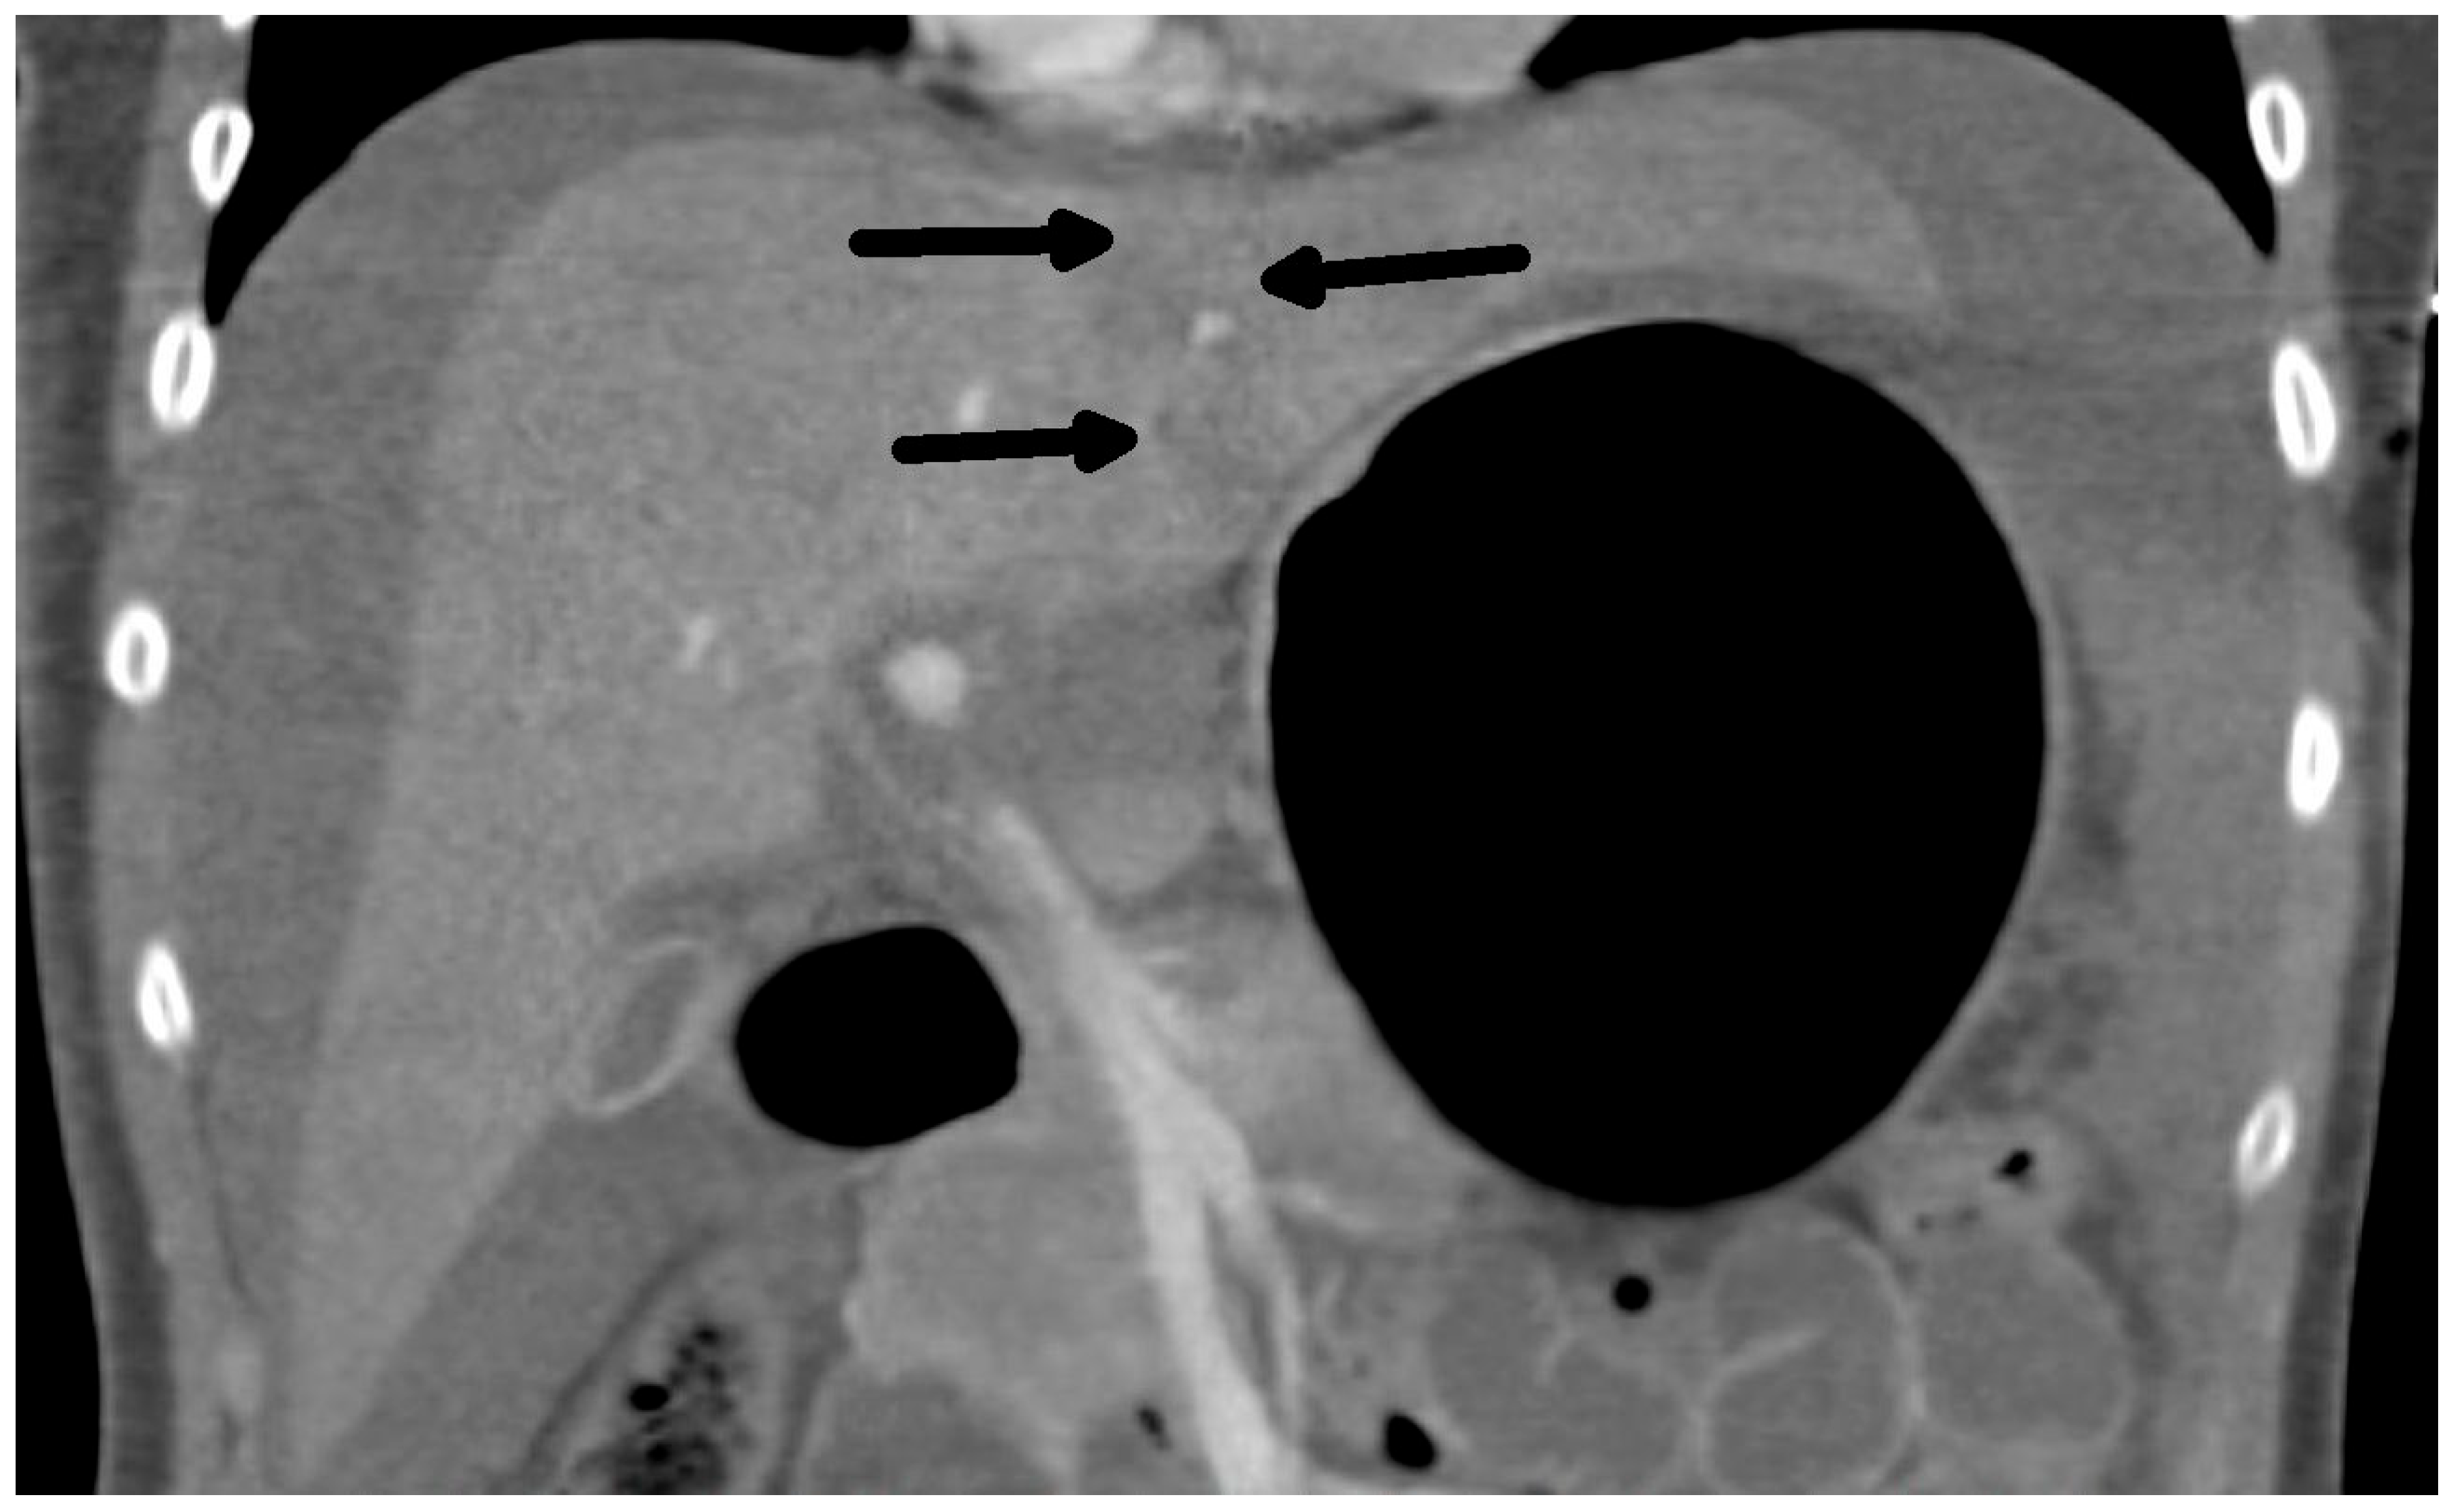

The diagnosis of liver injury was made by clinical and paraclinical examination and confirmed by imaging techniques. (computed tomography (CT) or ultrasound) (Table 2) (Figure 1 and Figure 2).

Figure 1.

CT scan: Rupture of the liver along falciform ligament (arrows) and hemoperitoneum transverse view.